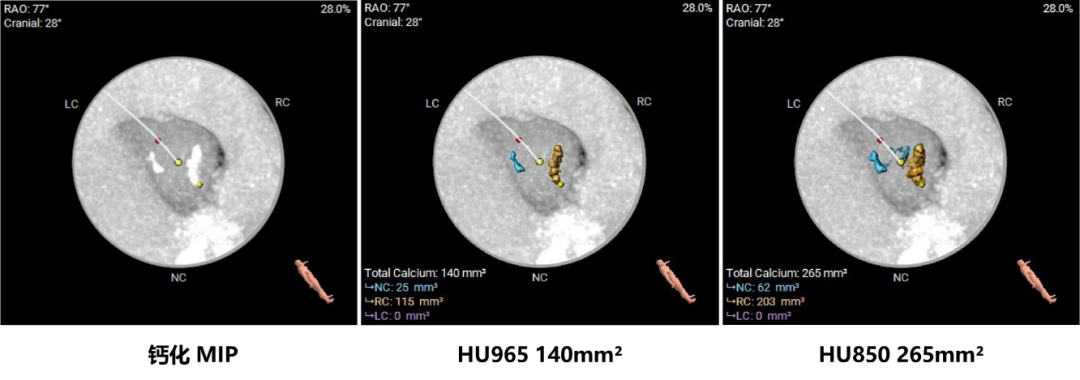

主动脉根部评估:

瓣环上结构测量:

该病例入路偏细,近横位心对瓣膜的输送系统的通过性和柔顺性都有较高要求;瓣上限制较多瓣架容易发生向下位移风险,需要瓣架具有良好的径向支撑力及顺应性,位移较多情况下瓣膜系统能够再次调整。